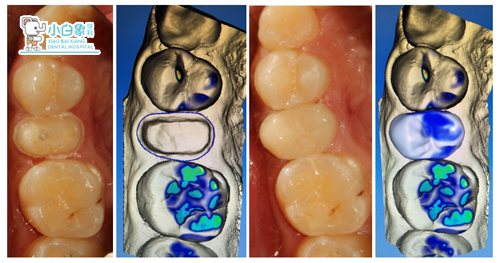

制备牙体,取像,设计,制作高嵌体,试戴,粘结。

戴牙